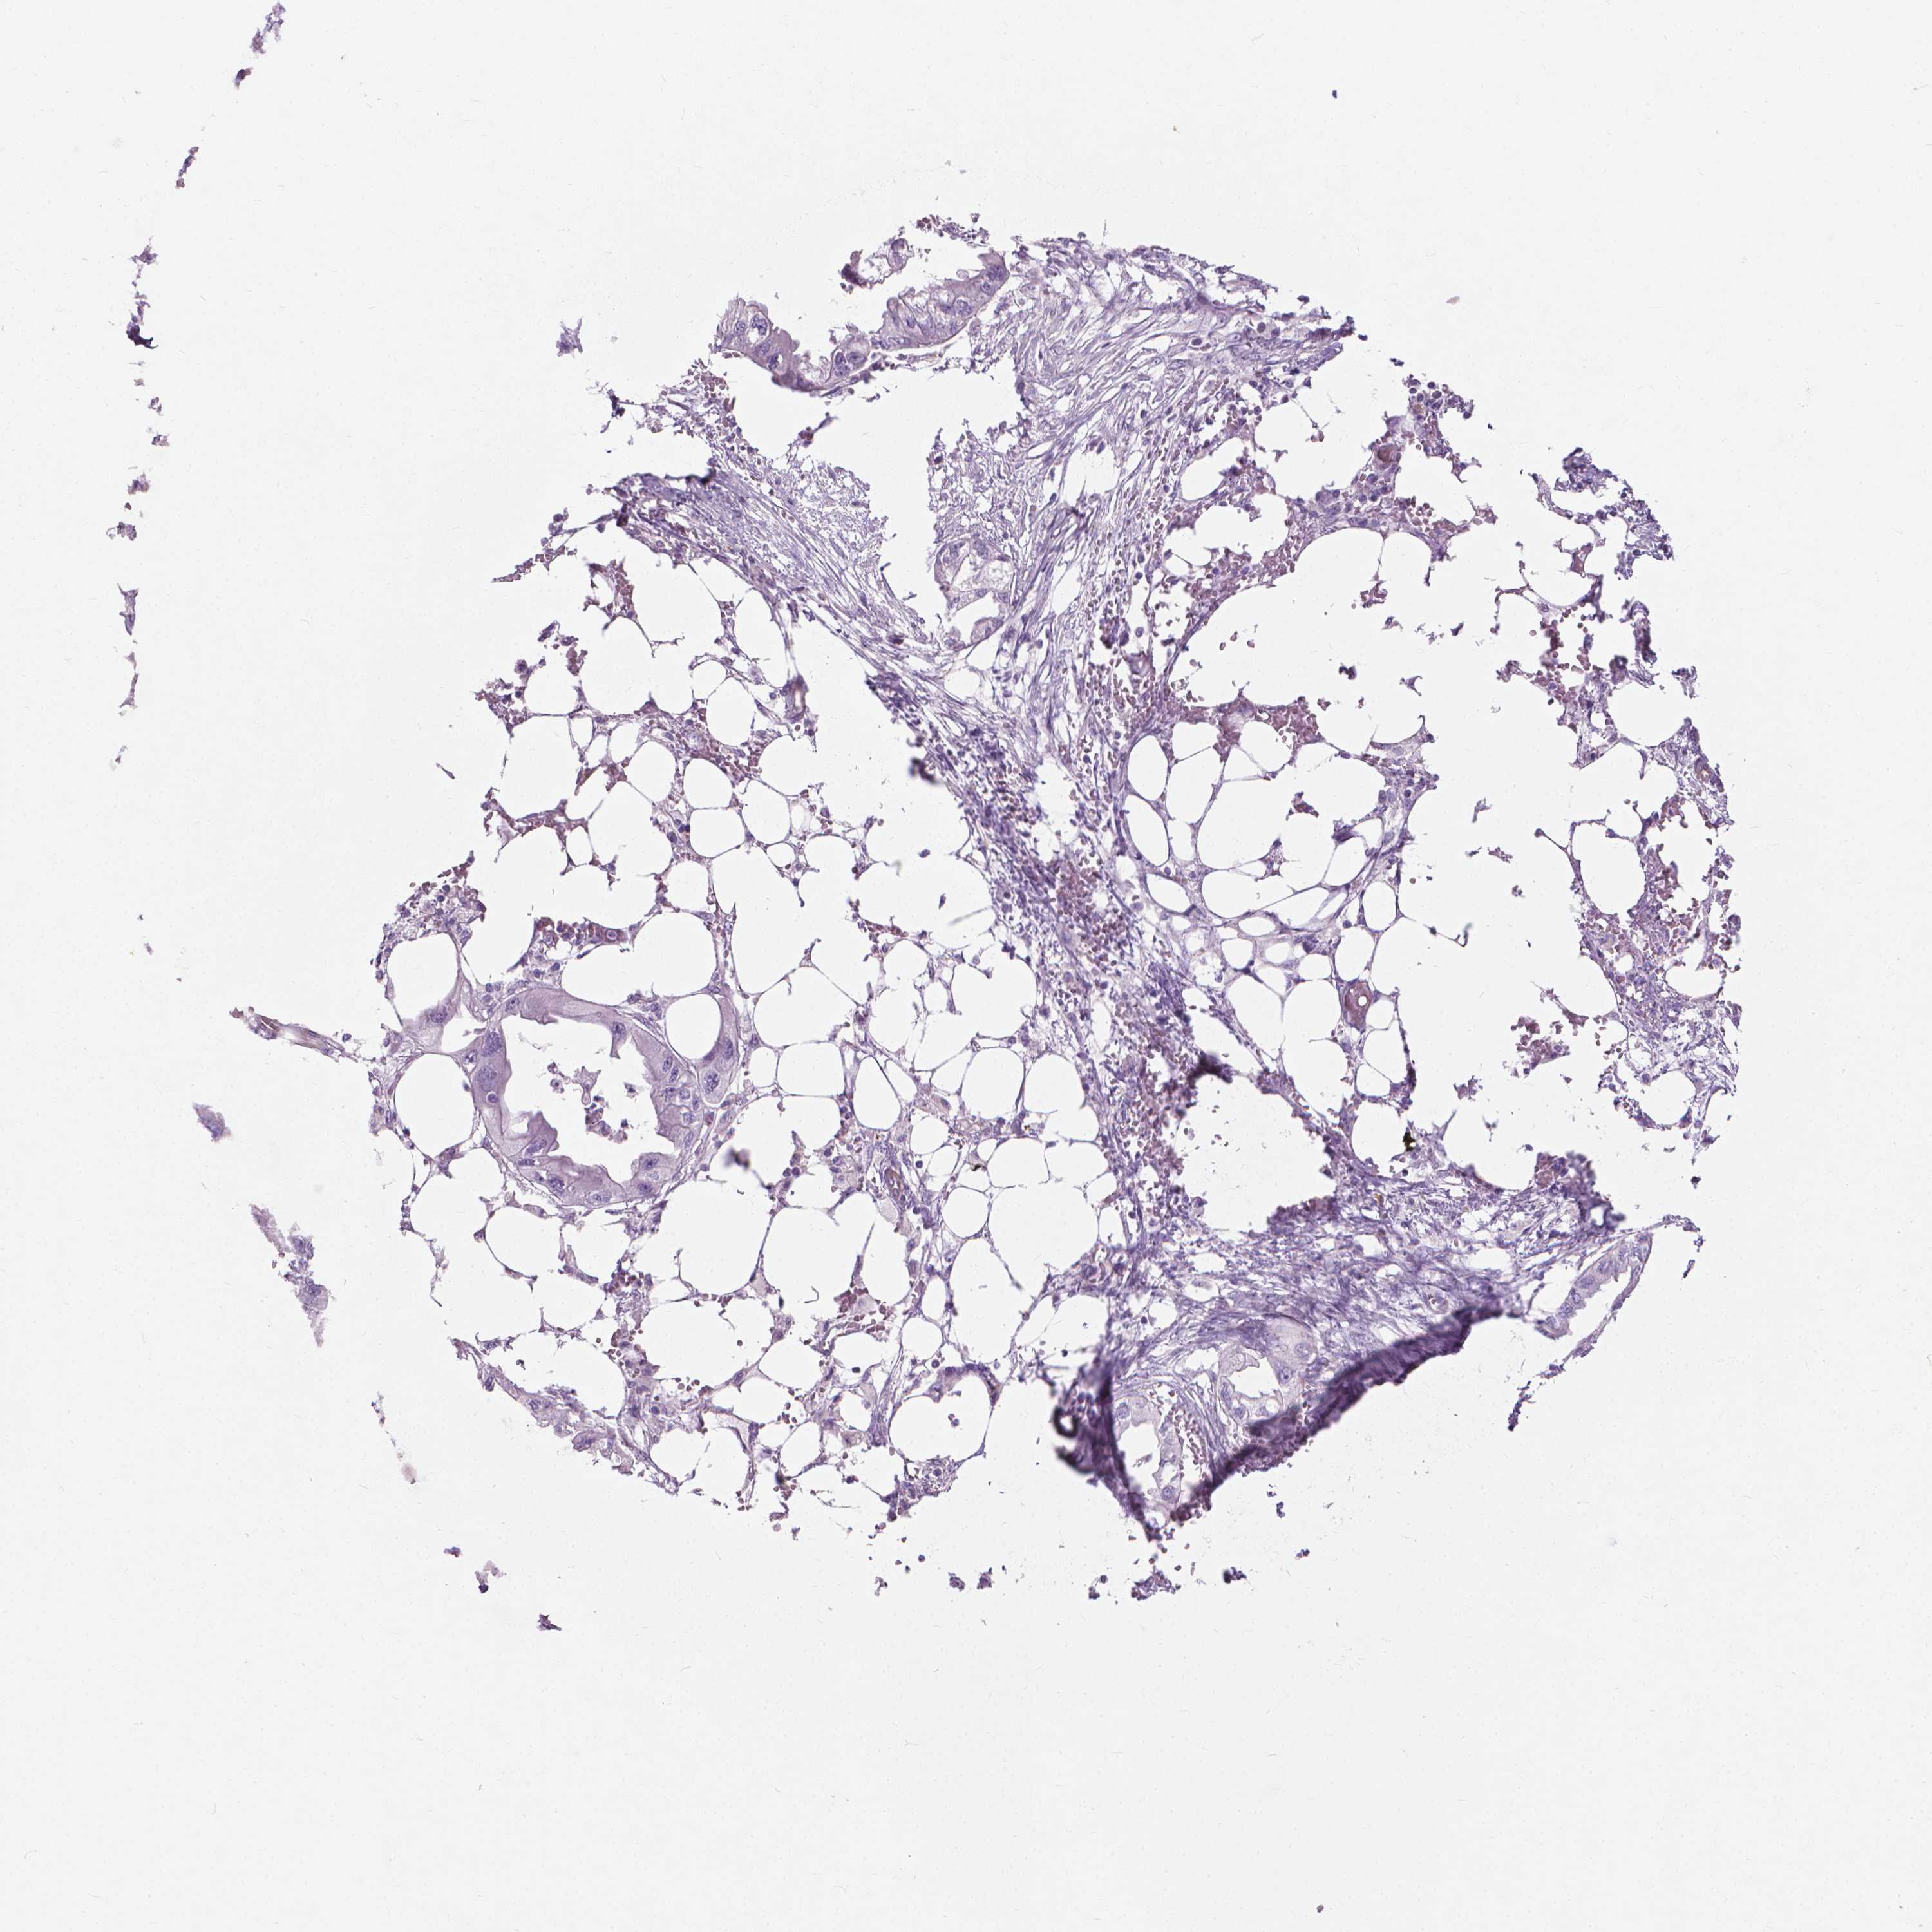

ENDOMETRIAL CANCER - Protein expressioni

A mouse-over function shows sample information and annotation data. Click on an image to view it in a full screen mode. Samples can be filtered based on level of antibody staining by selecting one or several of the following categories: high, medium, low and not detected. The assay and annotation is described here.

Note that samples used for immunohistochemistry by the Human Protein Atlas do not correspond to samples in the TCGA dataset.

Antibody stainingi

Antibody staining in the annotated cell types in the current human tissue is reported as not detected, low, medium, or high, based on conventional immunohistochemistry profiling in selected tissues. This score is based on the combination of the staining intensity and fraction of stained cells.

Each image is clickable and will lead to virtual microscopy that enables deeper exploration of all samples and also displays staining intensity scores, fraction scores and subcellular localization as well as patient and tissue information for each sample.

Antibody HPA044031

Staining

High

Medium

Low

Not detected

Intensity

Strong

Moderate

Weak

Negative

Quantity

>75%

75%-25%

<25%

None

Location

Nuclear

Cytoplasmic/membranous

Cytoplasmic/membranous,nuclear

Adenocarcinoma, NOS

Adenocarcinoma, metastatic, NOS